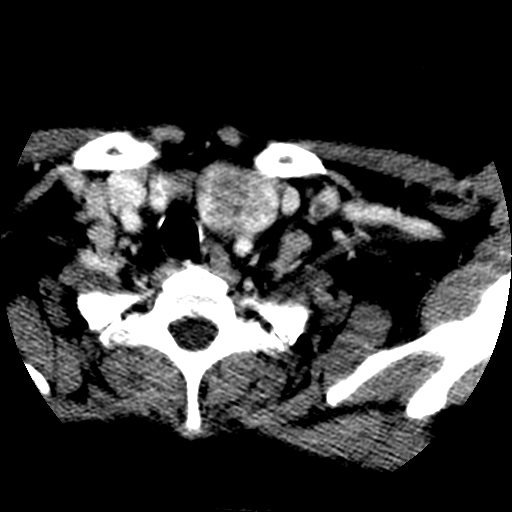

考虑左侧甲状腺结节性甲状腺肿,不排除甲状腺腺瘤。

考虑左侧甲状腺腺瘤囊变。